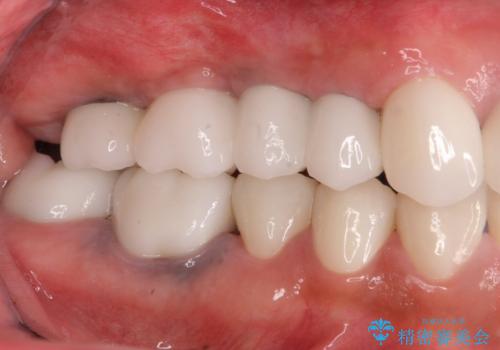

- 165万円(インプラント×3・チタンカスタムアバットメント×3・ジルコニアクラウン×4・仮歯×6)費用は治療当時の料金となります

長らく気になっていた歯ぐきの疼くような感じや、咬合機能が改善され、満足いただくことができました。